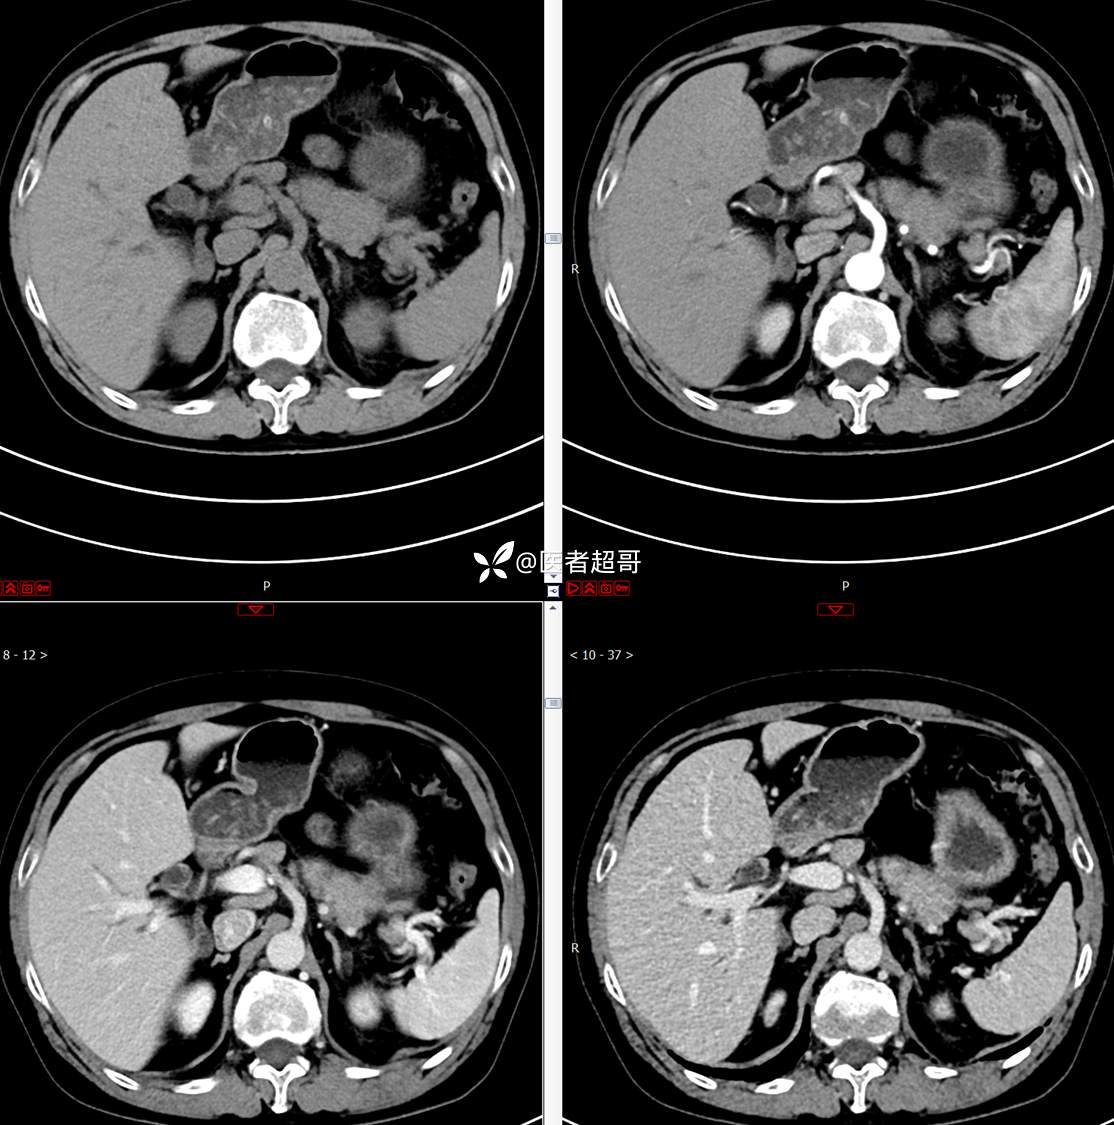

【影诊笔记772】腹痛就诊,发现肾脏病变,CT、MRI齐全,请高诊!

主 诉:间断腹痛15天

现病史:患者15天前无明显原因及诱因出现腹部疼痛不适,呈间断性钝痛,右下腹为著,无尿频、尿急、尿不尽,无发热、寒战,无腹胀。于市中心卫生院住院治疗,超声示:胰头低回声包块,胆系扩张,左肾囊肿,胆囊壁毛糙,胆囊内胆汁淤积。患者为求进一步诊治,遂以“肾盂肿瘤”收入院,患者自发病以来,神志清,精神可,饮食睡眠可,大便无明显异常,近期体重无明显增减。